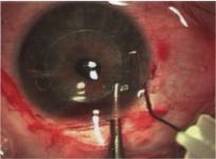

Surgical Treatment